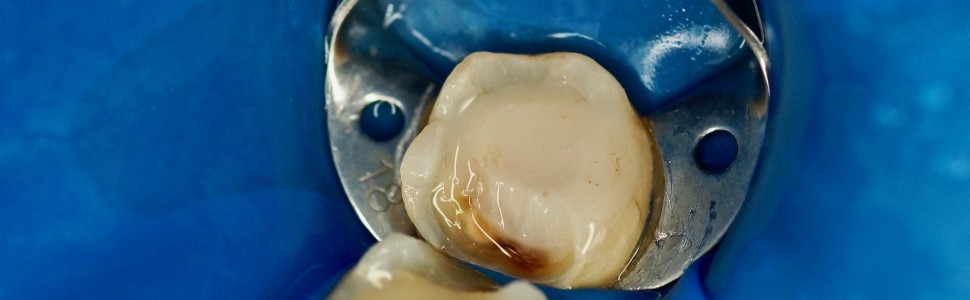

Artykuł omawia złożoną problematykę możliwości i ograniczeń wykonania napraw istniejących rekonstrukcji kompozytowych oraz ceramicznych. Na podstawie piśmiennictwa i doświadczeń własnych autor przedstawia argumenty oraz wskazania przemawiające za stosowaniem metod klinicznych umożliwiających przedłużenie żywotności zębów oraz wykonanych rekonstrukcji.

The article discusses the complex issues of the possibilities and limitations of repairing existing composite and ceramic reconstructions. Based on the literature and own experience, the author presents arguments and indications for the use of clinical methods to extend the life of the teeth and reconstructions.